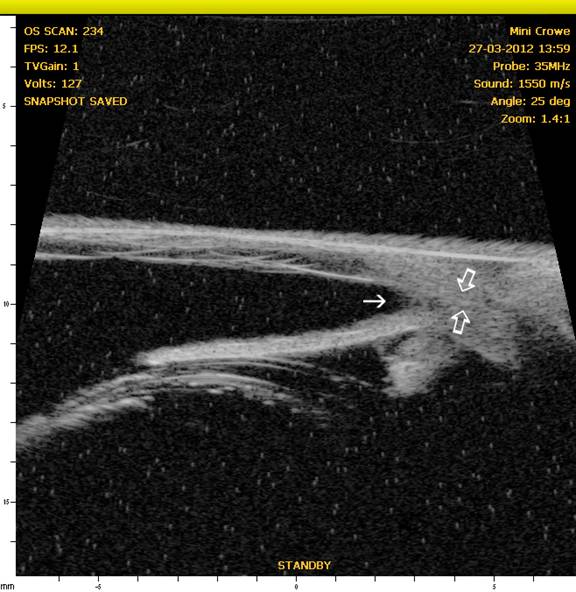

Ciliary Cleft

In recent years, through the use of high-resolution ultrasound (HRUS), we have been able to image the ciliary cleft where aqueous passes after it moves through the iridocorneal angle, and the results have revealed another factor that can contribute to increased intraocular pressure whether the iridocorneal angle is normal or not. In the following figures, note the differences in the ciliary cleft between the right and left eyes of a 10 year-old spayed female Boston terrier. The dog presented for cataracts and had a mature cataract in the right eye and an early immature in the left eye. At the initial examination gonioscopy revealed the iridocorneal angles were normal in both eyes. An electroretinogram was scheduled to evaluate retinal function (since the retina in OD could not be visualized) and prior to dark adaption the pupils were dilated with 1% tropicamide (a short acting anti-cholinergic mydriatic). The intraocular pressures (IOPs) were measured prior to and following dilation of the pupils. Prior to and following dilation the IOP in OD was 18 mmHg whereas the IOP in the left eye was 21 mmHg prior to dilation and 26 mmHg following dilation. HRUS revealed a normal ciliary cleft in the right eye with the mature cataract) and a markedly narrow ciliary cleft in the left eye with the immature cataract (See Figures 5 and 6.). Such occurrences illustrate the potential for problems with dilation of affected eyes as well as for an increased susceptibility for complications following cataract surgery.

Figure 6: OS – Note the normal iridocorneal angle (solid arrow) but narrow to nonexistent ciliary cleft (open arrows) accounting for the reason for the increased IOP in this eye after dilation.